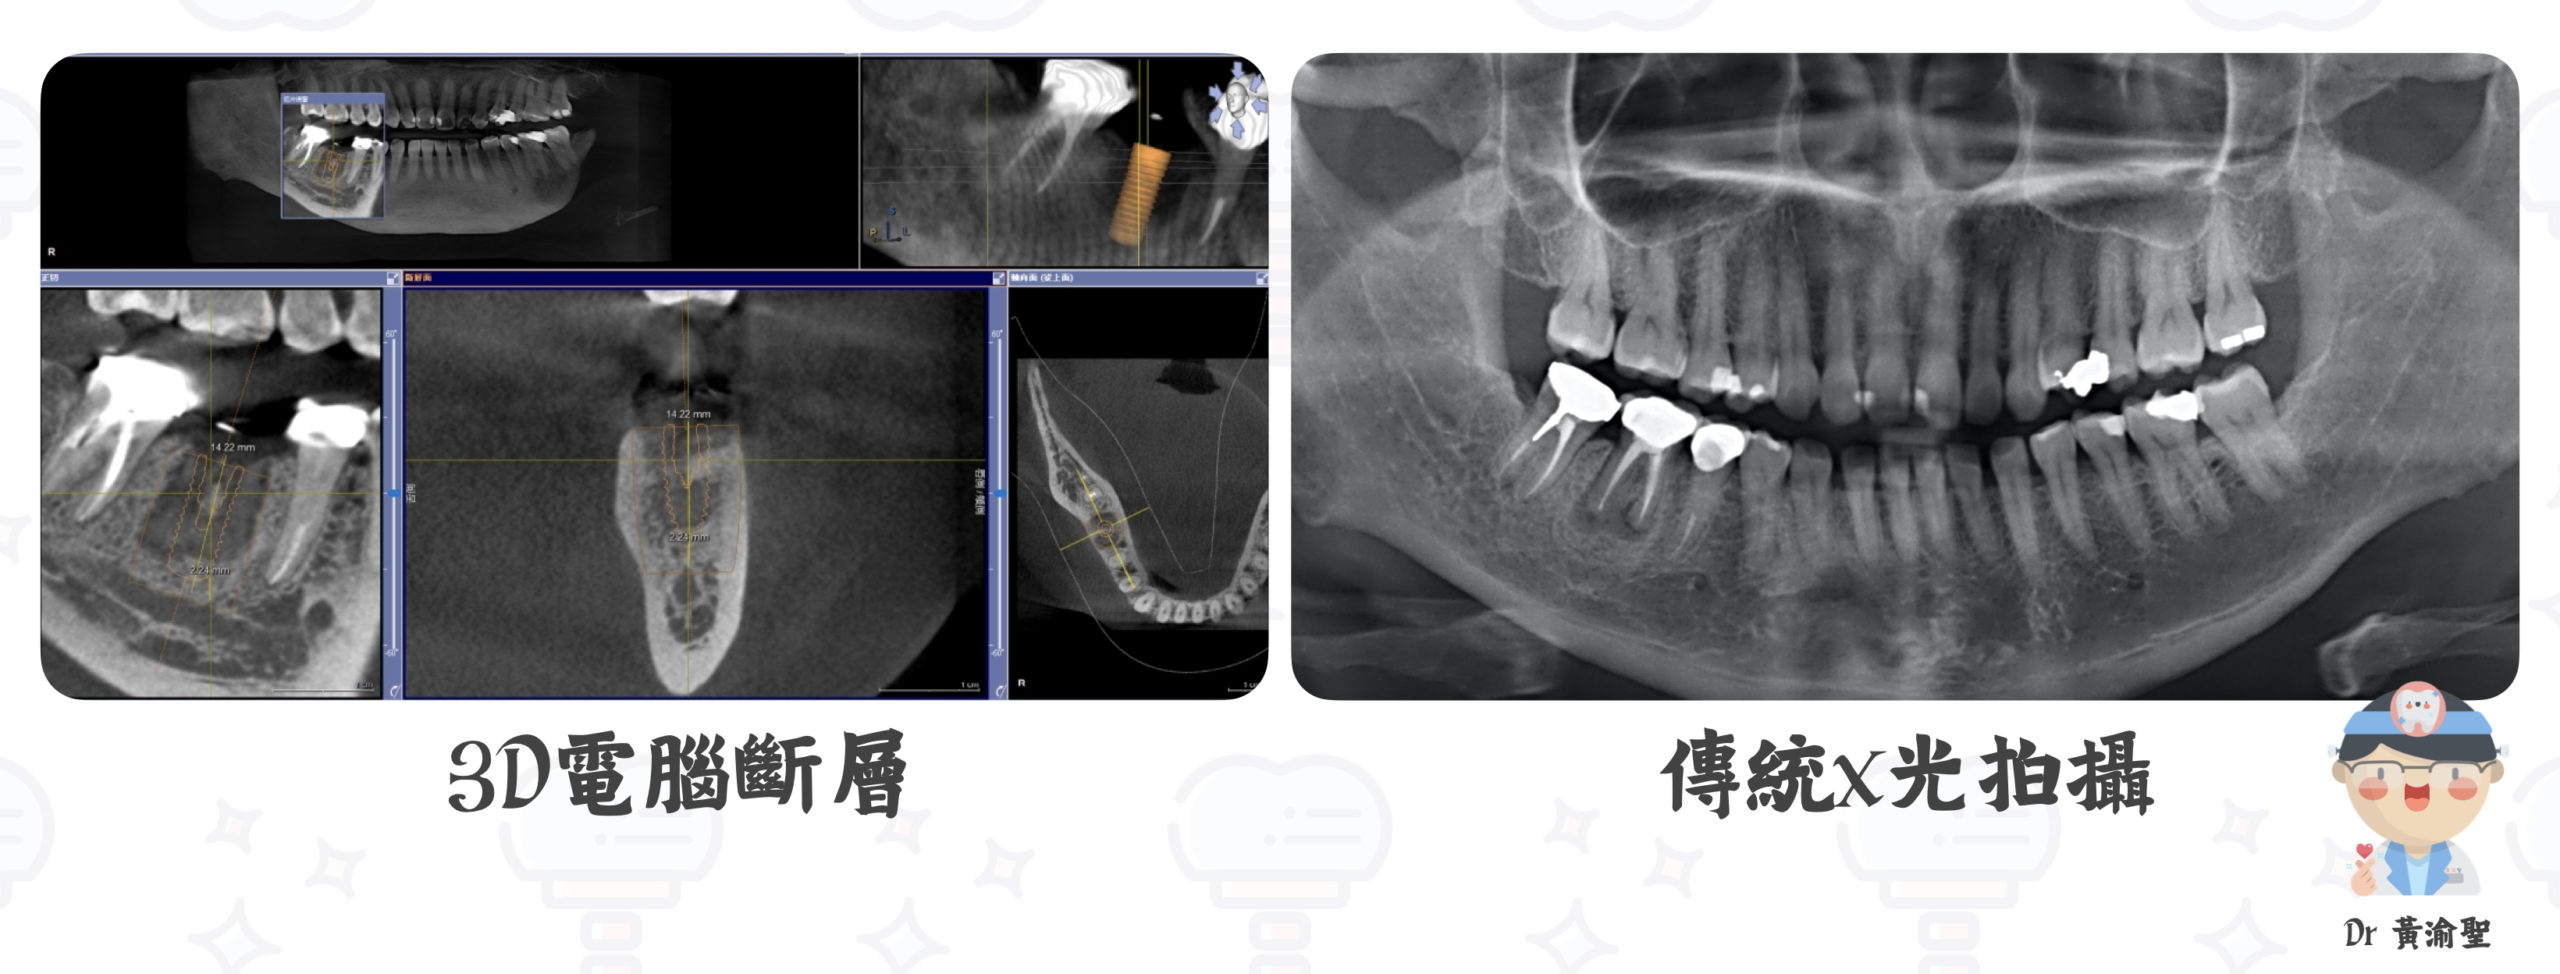

0 評論 0 FacebookTwitterTelegramLINEEmail 植牙是牙科突破性的發明 改變了牙科治療的方法 🤓🤓🤓 植牙是缺牙治療的一個選擇 植牙好處與牙橋相比 可以不傷害鄰牙 植牙過程 但植牙前往往會聽到親友說 啊~~那個植牙很貴 問題很多 誰誰誰失敗了 越聽越恐懼啊 植牙治療是需要仔細評估的 除了評估骨頭是否足夠 現在的文獻 證明了牙肉對於植牙成功 也會有很大的影響 植體的種類與型態 對植牙成果都會有影響 除此之外 口內咬合型態 缺牙原因 醫師都需仔細考慮 藉由x光拍攝及電腦斷層輔助 確認是否需要補骨頭 確認是否需進行牙肉移植手術 評估適當植體長度寬度型態 做好評估與治療可減少問題產生 植牙當然有可能會失敗 就像開車有可能出車禍 但在這之前 小心開車(不咀嚼太硬食物) 定期保養(回診) 添購好的防護設備(補骨頭補肉) 都能大大降低失敗機率 醫生我有內科疾病能不能植牙啊 多數疾病例如高血壓 糖尿病等 控制良好下對於植牙成功率沒有影響 但當骨質疏鬆有服用或注射藥物時 需由醫師評估是否適合植牙 抽煙 尼古丁 煙焦油影響傷口癒合 反而會明顯降低植牙成功機率 😧😧😧 在缺牙區進行植牙修復可以避免鄰牙受力過大 簡單來說就是 本來要三顆牙平均分攤咬合力 現在少一顆牙 旁邊牙齒就要多多出力了 圖示植牙為方便維修的螺絲孔植牙設計 植牙與車子很像 個人開車習慣 條件不同 需要不同的配備幫助 如補骨補肉 根據醫師建議使用植牙 小心開車(不咀嚼太硬食物) 定期保養(回診) 添購好的防護設備(補骨頭補肉) 可以減少植牙損壞機率 🚗🚗🚗 小黃醫師第一次去美國 就是到密西根大學進修植牙 (全美牙科第一) 在真實的人頭上進行手術模擬 🤫🤫🤫 是真的人頭歐 很特別 美國人比較開放 會簽立遺囑把自己遺體賣掉 等於留一份遺產給自己的親人 參加住院醫師晨會 感受學習風氣 受益良多 體驗到了美國麥當勞有夠大份的食物 到處都有很大台且很漂亮的卡車(像變形金剛) 順便看看美國人有沒比較大 歐 我是說買衣服的尺寸啦~ 分享簡單的案例給爸爸媽媽 如果您比您家寶貝害怕看牙 也有看牙需求 也歡迎爸爸媽媽掛號 (我們可以約小孩不在的時間看牙 哈哈) 跟小黃醫師討論討論歐 #黃渝聖醫師 #案例分享 #人工植牙 #兒童牙科專科醫師 #員林基督教醫院 #彰化基督教醫院 #全口重建 #游離齦移植術 人工植牙兒童牙科專科醫師全口重建員林基督教醫院彰化基督教醫院案例分享游離齦移植術黃渝聖醫師 0 評論 0 FacebookTwitterTelegramLINEEmail 上一篇 慢一點 可不可以-換牙延遲 下一篇 牙膏選購 刷牙小提醒 你可能也會喜歡 牙齦萎縮-牙肉移植術(軟組織移... 成人全口重建 讓治療可以被預測-數位美學分析... 陶瓷嵌體-保留齒質的好方法 前牙美學-每個人都值得擁有更美... 植牙前矯正治療 讓你的笑容更自然-前牙微笑調整 Turkey Teeth 土耳... 讓女孩綻放笑容的魔法-陶瓷貼... 美學陶瓷貼片 -隨時自信展露笑...